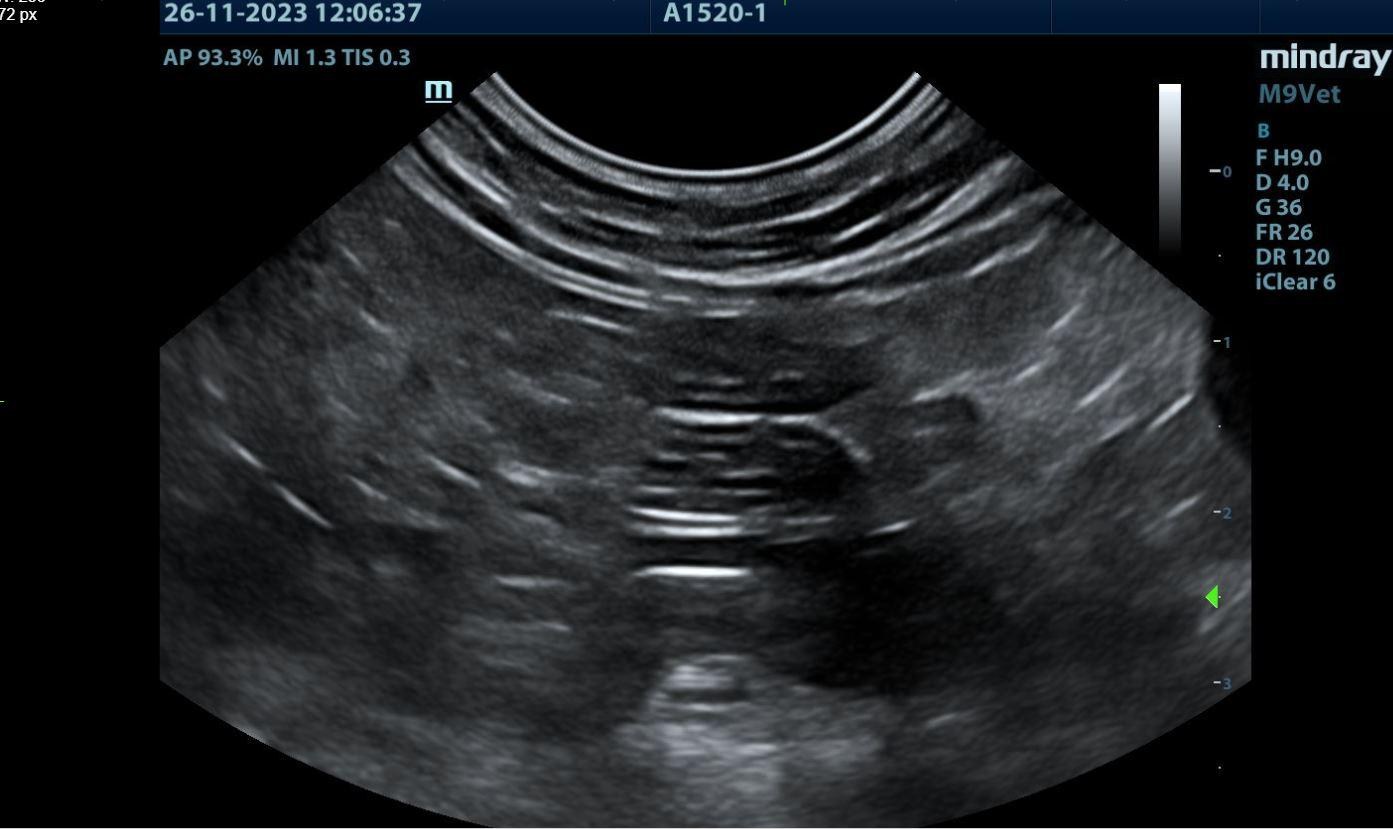

醫生說有東西卡住導致食物下不去(但我看不懂,甚至不曉得是否藉由這張超音波看出來的)

照超音波時為了不讓肋肋亂動,所稍微麻醉,但不是完全昏迷。看到他半昏沉的樣子躺在診檯上,有點不捨QQ

超音波抓到了疑似異物的確切位置,所以醫生說要動手術。